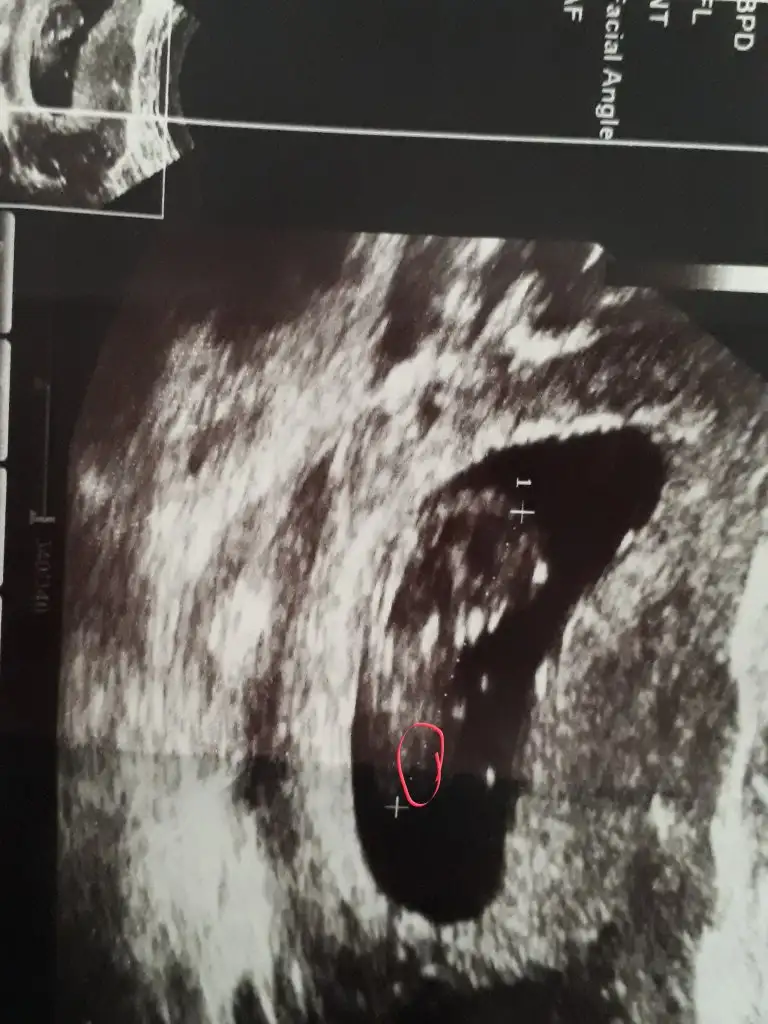

Ikram simdi gordum bu msjini ben bu isaretlediklerimi nub saniyorum kiz hala cozememisim desene nub degil bunlar galiba birde zaten birinde bana gore dik digerinde paralel sanki terzi misali kendi sokugumu dikemiyorum aklim erkekte ya her cikintiyi pipi saniyorum galibaSen daha iyi görüyorsun USG yi resim net değil sen ne diyorsunbebisine

Yok değil nub hiç belli değil canimIkram simdi gordum bu msjini ben bu isaretlediklerimi nub saniyorum kiz hala cozememisim desene nub degil bunlar galiba birde zaten birinde bana gore dik digerinde paralel sanki terzi misali kendi sokugumu dikemiyorum aklim erkekte ya her cikintiyi pipi saniyorum galiba

Zaten ben sizden 11 12 13 haftalar istedim (tutmayabilir) yazdimanlamadigim, nub genital bilge olusana kadar gorulen birsey, peki benim 14 uncu haftada neden hala nub gorunuyr.Genital bolge olusmus olmasi gerekmiyormu